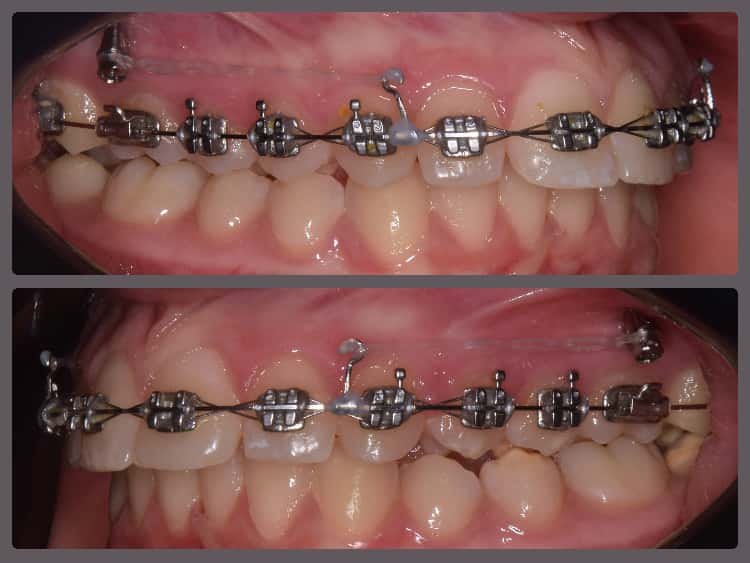

Péter súlyos nyitott harapása miatt szeretett volna fogszabályozót. A kezdeti diagnosztikát követően a nyitott harapáson túl felső fogívszűkületet és enyhe alsó torlódást állapítottam meg. Péternél funkcionális probléma is a felszínre került: nyelvlökéses nyelése volt. A nyelvlökéses kezelés terápiájában logopédus volt segítségünkre, “negatív megerősítésként” pedig a felső metszőfogak belső felszínére ragasztottam nyelvlökés gátló tüskéket. Ilyen esetben a nyitott harapás kezelésénél kulcsfontosságú eldönteni, hogy a harapási eltérés fő oka az állcsontok rendellenes pozíciója, vagy csupán a fogak/fogmedernyúlvány nem megfelelő helyzete. Péter esetében szerencsére főként az utóbbi volt látható, ezáltal nem volt szükség állcsont műtéttel egybekötött fogszabályzó kezelésre. Alsó-felső H4 önligírozó rögzített fogszabályozó készüléket alkalmaztam Péter kezelésénél. A bracketeket az átlagostól “magasabbra”, közelebb az ínyhez ragasztottam. Ez nem csak a mosoly esztétikát javította, hanem a nyitott harapás megoldásában is nagy segítségünkre volt. Péter végig nagyon együttműködő volt, megfelelően hordta az intermaxilláris gumihúzást, és a logopédiai kezelése is szépen haladt, ennek köszönhetően 17 hónap alatt végeztünk a fogszabályzásával! Úgy gondolom, hogy az elért végeredmény kiemelkedően látványos lett!